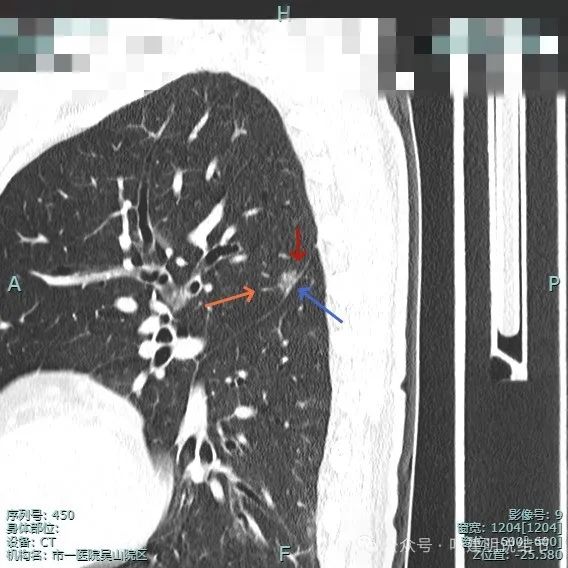

这种样子的混合磨玻璃阴影可直接切肺叶,甚至不必穿刺或活检,太典型了!

病史摘要:主诉发现肺占位半月余,复查胸部CT显示左肺上叶实性类结节影,患者从内科转入,内科已穿刺活检明确为恶性。诊疗过程:体格检查未提及。辅助检查方面,PET-CT 示左上叶尖后段占位,葡萄糖代谢增高,考虑恶性病变可能性大。影像显示病灶为混合密度,有胸膜牵拉、血管增粗等典型浸润性癌表现。杭州市第一

明明典型浸润性癌影像表现病理结果却是原位癌,原位癌也可表现为混合密度?

病史摘要:患者 3 个月前社区体检发现肺结节,就诊时医生考虑左上病灶基本为肺癌且倾向浸润性,因首次发现,建议口服抗炎 10 - 12 天,间隔 3 个月复查。此次复查无吸收好转及明显进展,拟手术治疗。诊疗过程:体格检查未提及。影像检查显示左上叶胸膜下混合密度结节,有血管弯征、胸膜牵拉等诸多恶性特征,下叶有次病灶。临床考虑左上叶病灶恶性且浸润性癌可能性大,建议手术。术中快速切片报腺癌